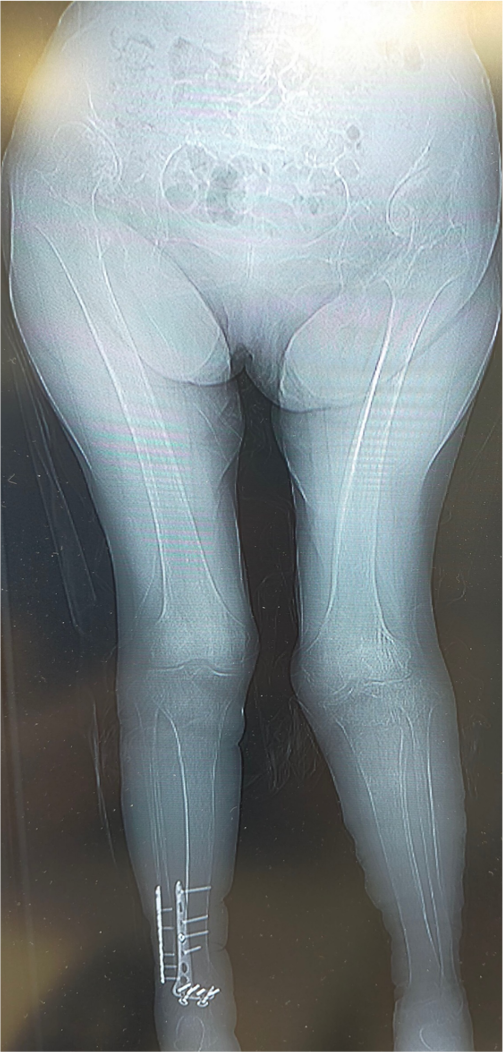

〈手術前のレントゲン〉